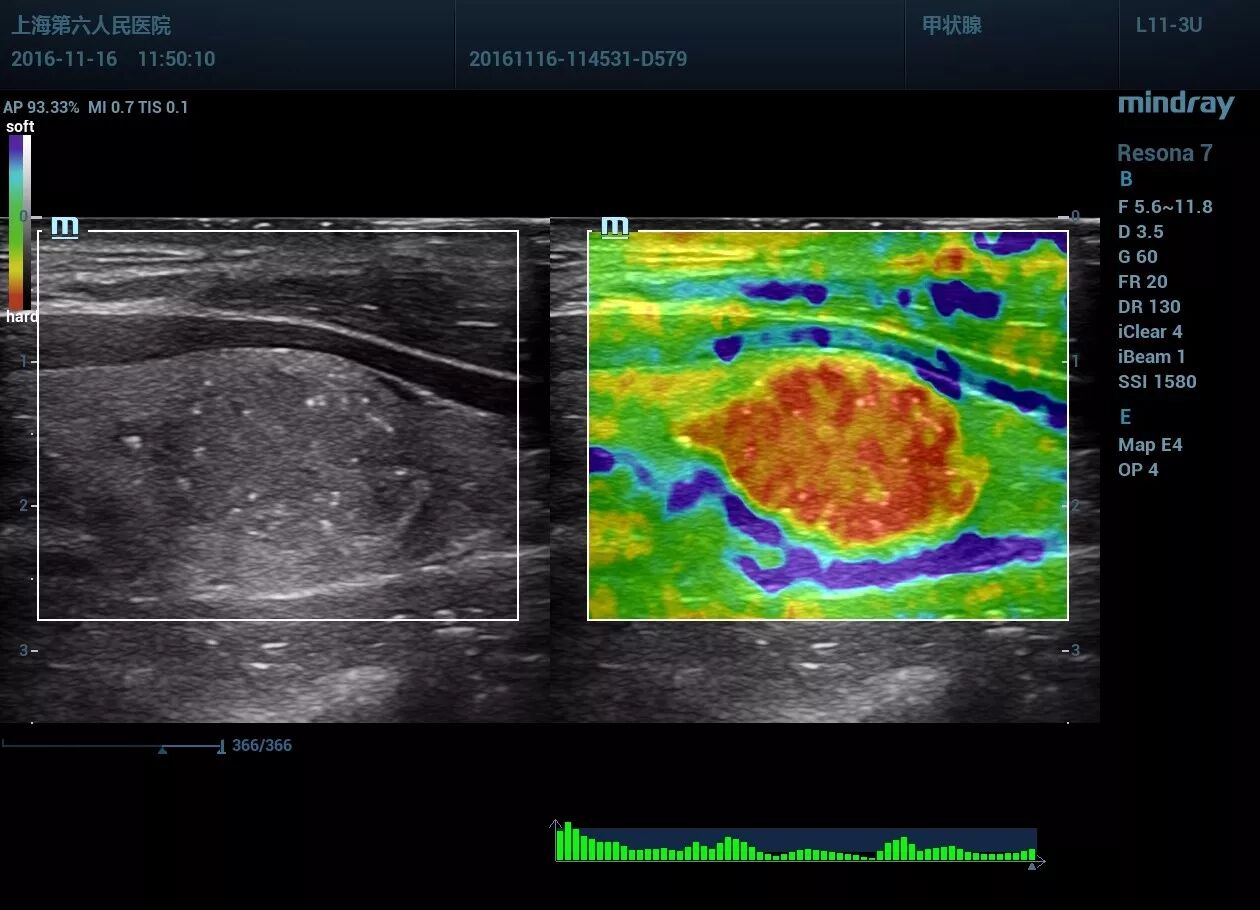

甲状腺左叶见一低回声区,大小约14*13*18mm,形态尚规则,部分边界欠清晰,内见点状强回声。CDFI显示血流信号丰富。左侧颈部VI区一淋巴结见高回声区。

应变式弹性评分:5分。剪切波弹性,横断面Emax94kpa,纵断面Emax123 kpa,远远大于良性病变的杨氏模量范围。纵切面显示肿块周边见深红色的不连续“硬环”。

1.甲状腺左叶实性结节伴微小钙化,弹性评分硬度高,考虑甲状腺Ca可能。